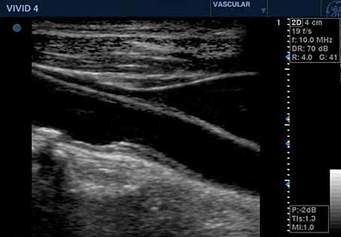

Bei Gefäßuntersuchungen handelt es sich meistens um sogenannte dopplersonographische Diagnostik. Hierbei kann man die Fliessgeschwindigkeit des Blutes messen, die bei verengten Gefäßen besonders hoch ist. Im Duplexverfahren lassen sich diese Veränderungen auch im Bild darstellen. (siehe Abbildung) |